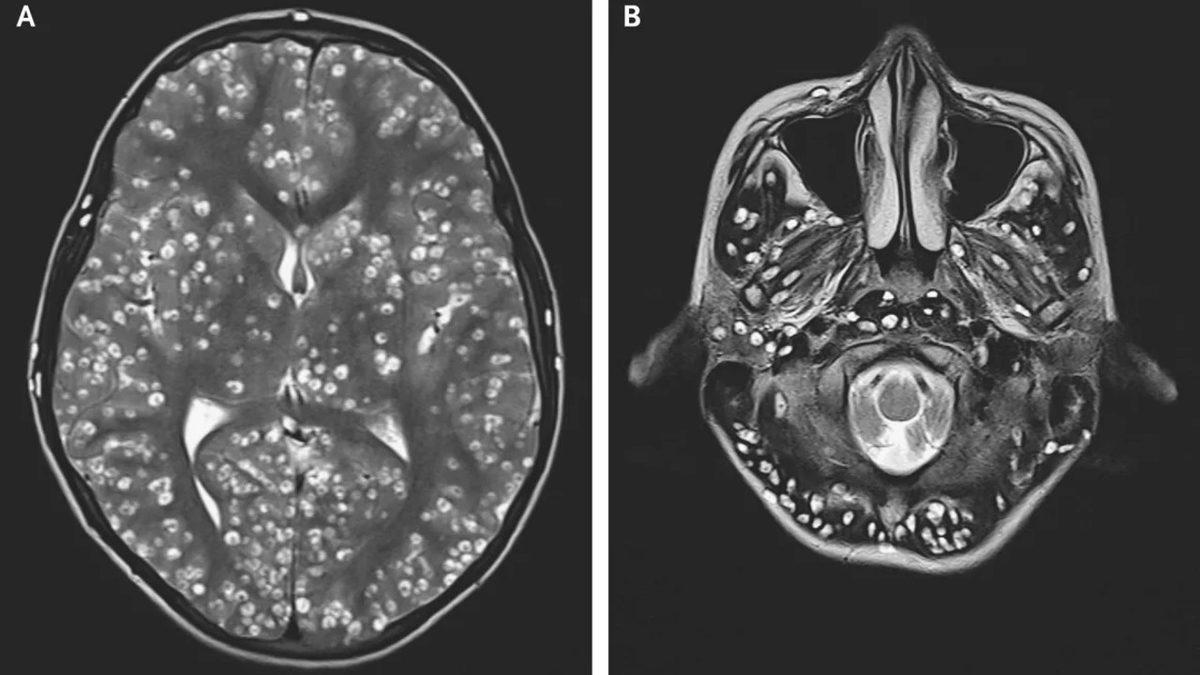

MR taraması yapılan ve beyninin MR'ı çekilen 43 yaşındaki Zhu Zhong-fa’nın beynindeki ve vücudundaki tuhaflıkların sebebi bir tümör falan değildi. Aslında epey korkutucu bir şeye dayanıyordu.

Çin’in Hangzhou şehrinde yaşayan adam, kendinde tuhaf semptomlar fark etmişti ve belirtileri başladıktan yaklaşık 1 ay sonra hastaneye gitmişti. Doktorlar, neyin yanlış olduğunu ilk başta anlamadılar. Taramaları artırdıklarında ise sorunun kaynağı, gün yüzüne çıktı.

Adam 1 ay önce, az pişmiş domuz eti yemişti ve etteki parazit larvaları vücutta birikerek merkezî sinir sistemini istila etmişti. Zhu Zhong-fa’nın beyninde, akciğerlerinde ve göğüs boşluğunda 700’den fazla solucan kıvrıla kıvrıla geziyordu!

Nörosistiserkoz adı verilen bu enfeksiyona daha yakından bakalım.

Az pişmiş domuz etinin vücudumuza parazitler bırakmasıyla gelişen nörosistiserkoz; merkezî sinir sisteminde, kaslarda, ciltte ve gözlerde birikebilir. Az pişmiş domuz eti yiyen bir kişi, tuvalete gittikten sonra ellerini düzgün bir şekilde yıkamazsa mikroskobik solucan yumurtalarını yutabilir.

Yumurtaları yuttuktan sonra ise larvalar, yumurtadan çıkarlar ve bağırsak duvarına nüfuz ederek vücudun diğer bölgelerine yayılırlar. Böylece yukarıdaki beyin MR'ında görebileceğimiz manzaralar ortaya çıkabilir. Beyindeki ve vücudun diğer bölgelerindeki solucanları öldürmek için ilaç tedavisi uygulanır fakat nadir de olsa ölüme kadar gidebilir.